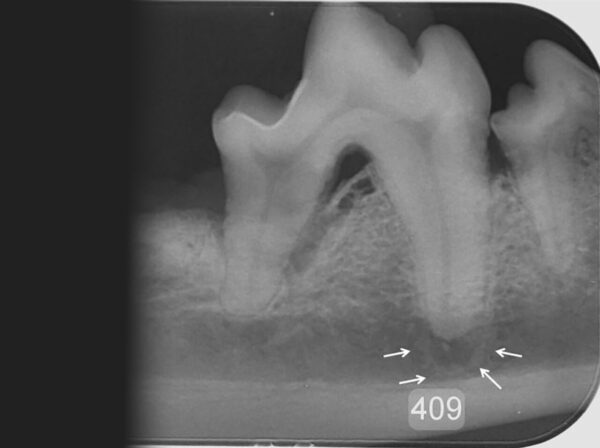

- Como parte del planteamiento quirúrgico previo a la realización de extracciones dentales, ya que nos permitirá detectar alteraciones no percibidas en la exploración visual directa, lo que hace posible una mejor planificación del abordaje del diente a exodonciar y reduce las complicaciones posquirúrgicas. También será de gran utilidad la obtención de imágenes posexodoncia que nos permitan evaluar que el procedimiento se ha realizado correctamente sin que existan restos de estructuras dentales que puedan dar lugar a complicaciones en el futuro (imagen 24).

De hecho, estudios realizados por Verstraete y cols. (1998), tanto en el perro como en el gato, determinan que en las evaluaciones radiológicas dentales se diagnostican lesiones clínicamente importantes (27 % en perros y 41 % en gatos) cuando no hay hallazgos clínicos presentes en el examen intraoral. Por su parte, en un estudio realizado en 147 gatos con periodontitis, Lomer (2001) halló que un 25,2 % tenían evidencia de pérdida periodontal más grave de lo esperado en la exploración física. Además, Moore (2014) en sus estudios en 42 gatos que habían sido sometidos a la extracción de los 4º premolares maxilares (108 y 208) y de los 1º molares mandibulares (309 y 409) encontraron que el 92,8 % de los casos presentaban fragmentos de puntas de raíz retenidas.